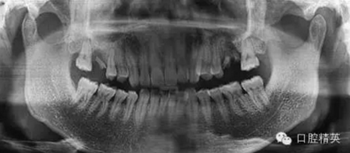

拔除前曲斷

X線顯示左上頜6殘根,慢性根尖周圍炎波及上頜竇底,行拔除殘根處理,囑術后常規(guī)消炎。